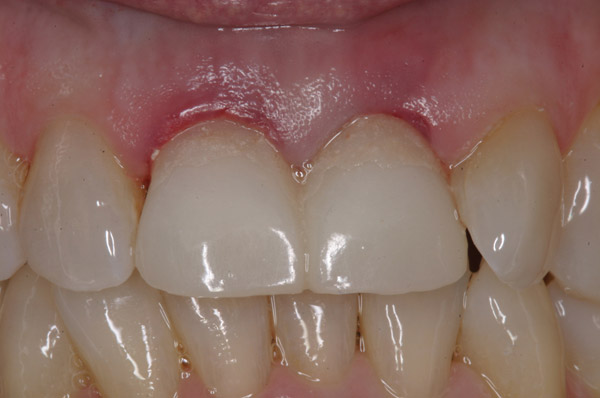

Figure 1  Initial presentation. Teeth Nos. 8 and 9 had internal and external resorption and were deemed hopeless. Recession of 4 mm was associated with tooth No. 9.

Figure 1

Figure 2  The orientation of the healing abutments after the patient had undergone extraction, guided bone regeneration, and implant placement. Note the wide spacing between the central incisor implants.

Figure 2

Figure 3  Periapical radiograph of implants in the Nos. 8 and 9 sites 3 years after placement. A bony peak was still present between the implants due to successful guided bone regeneration and favorable fixture spacing.

Figure 3

Figure 4  Final restoration of implants in the Nos. 8 and 9 sites 3 years after placement. Note the short central papilla regardless of the presence of bone. Restoration courtesy of Dr. Alan Goldberg.

Figure 4

Figure 5  A naturally low smile line hid the clinical “black triangle” from view.

Figure 5